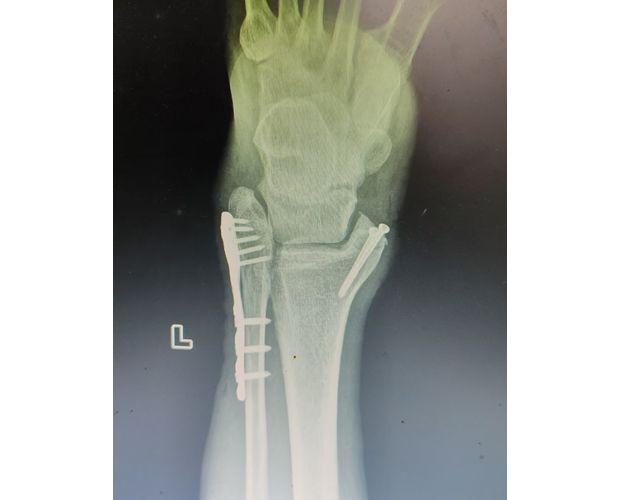

本次帮扶由曾都区人民医院脊柱创伤神经外科主任徐三军带队,专家团队抵达后立即完成手术风险评估及术前准备。手术过程中,徐三军主任严格规范完成各项手术操作,并同步结合手术步骤,为该院外科医师详细讲解骨折手术的关键要点、操作技巧、术中注意事项及术后康复要领。通过“手把手”的实战带教,专家将丰富的手术经验与规范的诊疗思路倾囊相授,让该院医护人员在实操中学习,在过程中成长。

此次医共体专家下沉帮扶,不仅成功为患者解除了病痛,让群众在家门口即享优质、便捷的三甲医院专科手术服务,更通过“手术带教、现场指导”的实战模式,显著提升了该院在骨折诊疗和手术操作等方面的专业能力,为基层医疗服务水平提升注入强劲动力。